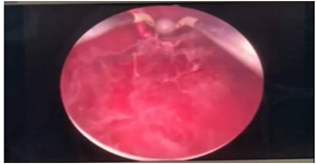

Cystoscopy was done to detect mucosa lesions in bladder; the whole mucosa was congested and red. There were multiple hemorrhagic areas in whole bladder mucosa; it was bled on touch. There was no focal ulcer or tumor. Therefore, generalized congested mucosa, hemorrhagic areas were probably due to DIC or CMV cystitis or candida cystitis or bacteria cystitis. The color of urine coming from Vescio-ureteric orifice of graft kidney was clear. Hemostasis was done with Ball electrode; bladder wash out was done with Tomey’s glass syringe. Figure 9-15 reveal cystoscopy findings. Abdominal tomogram was done; it revealed a swollen allograft kidney with air in the renal pelvis and renal vessels and subcapsular area suggestive of emphysematous allograft pyelonephritis. And, air along bladder wall was seen indicating emphysematous cystitis. They are illustrated in (Figure 16-19).